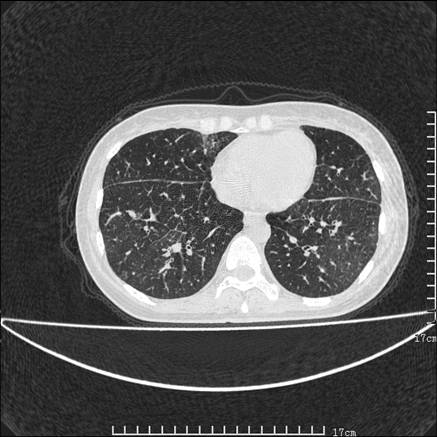

双肺小叶间增厚,双肺散布粟米影和磨玻璃状影,以双肺上叶为重。结合病史考虑转移(癌性淋巴细管炎)可能性大。

结合病史:认为是典型肺部癌性淋巴管炎、淋巴结转移。请看图解。

肺癌性淋巴管炎征象分为主要征象及合并征象,主要征象包括:

1、近肺门支气管血管周围间质结节状增厚;

2、小叶间隔结节状增厚;

3、小叶中央间质结节状增厚;

4、胸膜下间质结节状增厚。

合并征象为:纵隔淋巴结增大,胸腔积液,肺多发随机分布的小结节等。